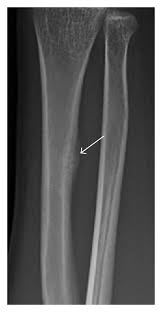

피로 골절이 자주 생기는 부위

피로 골절은 반복적으로 체중이 실리는 부위에서 흔히 발생합니다. 특히 아래 부위는 비교적 자주 언급됩니다.

• 정강이 뼈 주변